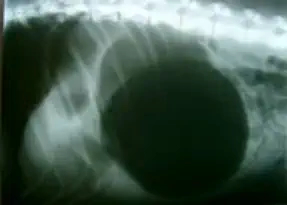

Eine Magendrehung mit einer damit verbundenen Verschlechterung der Magenwand aufgrund einer verminderten Durchblutung

Bestehen Sie in diesem Fall immer auf einer Röntgenaufnahme des Unterleibs. Ein verdrehter Bauch ist darauf immer deutlich als schwarzer Ballon zu sehen.